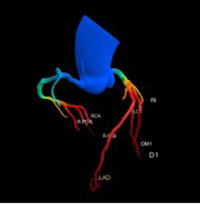

通过冠脉CTA,能清晰地看出多种心脏相关疾病:

最常见的是冠状动脉粥样硬化,也就是常说的“血管变窄”;

还能发现血管内的斑块,判断斑块的大小和稳定性,预警心肌梗死;

还能排查冠脉畸形、血管闭塞等,为临床治疗提供精准依据。